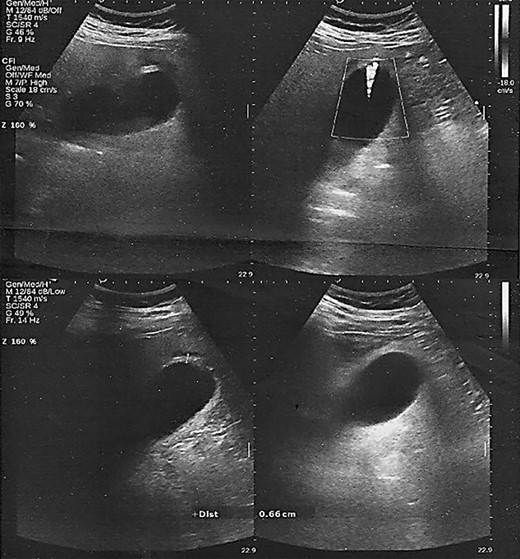

Laboratory examinations highlighted a normal leukocyte count (WBC 10.70 K/μl) and C-reactive protein levels (CRP 5.49 mg/L). However, an abnormal biochemical liver profile (SGOT 52 IU/l, SGPT 119 IU/l, γ-GT 117 IU/I) and ferritin (486 ng/ml) was noted. Nasopharyngeal swab-PCR was positive for SARS-CoV-2 infection. Chest X-ray showed interstitial lung infiltrations, whereas abdominal ultrasound identified a moderate gallbladder wall thickness without the presence of pericholecystic fluid or gallstones (Fig. 1).

Ultrasound scan. Gallbladder wall thickening without the presence of pericholecystic fluid or gallstones.